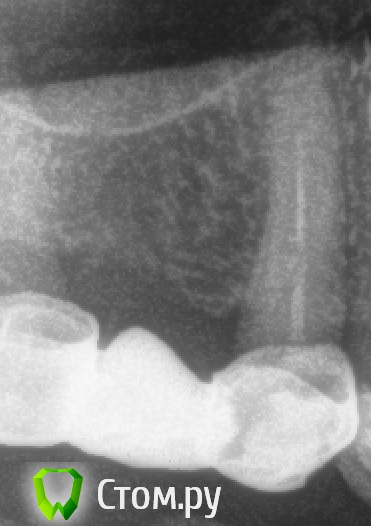

Каплан Опубликовано 27 мая, 2014 Автор Поделиться Опубликовано 27 мая, 2014 (изменено) эндо-история одного пациента.2.6 я анонсировал ранее. свищ, пропущенная анатомия мб2, провел через кальций. свищ закрылся через неделю, но пришлось потянуть подольше - не было окна для записи 3.6 хронический асимптоматический пульпит. старая "перфорация" под пломбой, вторичный кариес и все такое. один визит. 4.6-4.5 - провел через кальций. в 4.6 во второй визит решил дополнительно еще разок пройти 35.04. пациент прикрыл рот. 4 мм файла пришлось захоронить в апексе мб но отбайпасил до 25.04 почти до самого апекса (на 1 мм меньше рд).4.5 без петтенси. http://imagizer.imageshack.us/v2/xq90/841/f6j1.jpg http://imagizer.imageshack.us/v2/xq90/843/i9iw2.jpghttp://imagizer.imageshack.us/v2/xq90/841/3quaz.jpghttp://imagizer.imageshack.us/v2/xq90/844/dl2w.jpg Изменено 27 мая, 2014 пользователем Каплан 3 Ссылка на комментарий